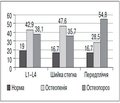

Паньків І.В. — Буковинський державний медичний університет, м. Чернівці

Журнал «Травма» Том 16, №4, 2015

Рубрики:

Травматология и ортопедия